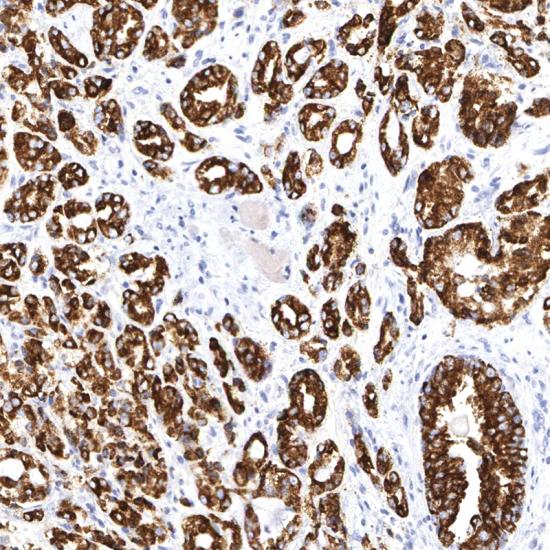

AMACR/P504S是一個(gè)參與分支脂肪酸β氧化作用的酶。表達(dá)于惡性前列腺腫瘤,而良性的前列腺組織不表達(dá)。在前列腺的癌前期病變、高級(jí)別的前列腺上皮內(nèi)腫瘤(PIN)以及不典型的腺瘤樣增生中亦有表達(dá)。P504S可用作PIN的陽性標(biāo)記物,它可用于穿刺活檢中小灶性前列腺癌的診斷。

AMACR/p504s

• 陽性部位:

細(xì)胞漿

• 陽性對(duì)照:

前列腺癌